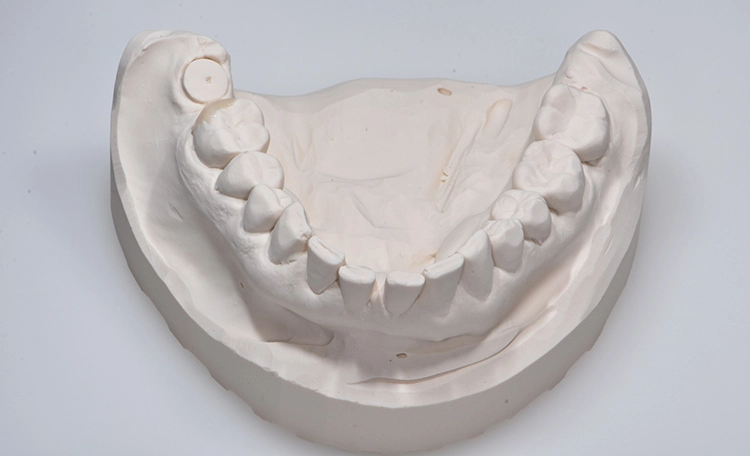

Nach der Alginat-Abformung folgte die Modellerstellung der Ausgangssituation (Abb.2). Mithilfe des Unterkiefermodells wurde ein individueller Abformlöffel mit einer Perforation im Bereich 47 für die spätere Implantat- und Pfeilerabformung angefertigt sowie eine Abformung mit EXACLEAR (GC) (Abb. 3) für die provisorische Versorgung der Zähne 45 und 46 – letzteres mittels handelsüblichem partiellen Abformlöffel.

Bilder: Dr. Lampson / HannkerAbb. 2a: Gipsmodelle. Bei Zahn 46 wurde Wachs hinzugefügt, um die Form im distalen Bereich zu verbessern.